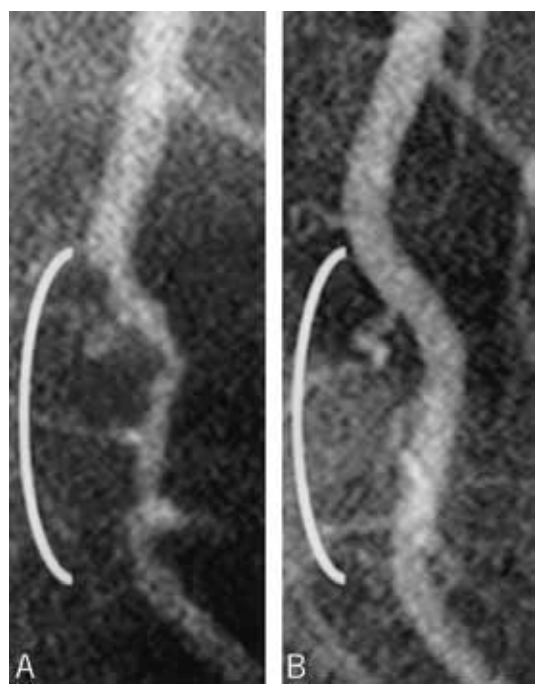

- Regressing fatty deposits or atherosclerotic soft plaques in blood vessels to reduce risk of further clogging, claudication and heart attack (refer to the section above on coronary artery disease) by lowering VLDL, sdLDL, LDL, ApoB and triglyceride levels in the blood.

- Regressing fatty deposits or atherosclerotic soft plaques in blood vessels to reduce risk of further clots and strokes (refer to the section above on coronary artery disease) by lowering VLDL, sdLDL, LDL, ApoB and triglyceride levels in the blood.